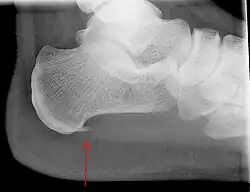

Radiografias com visão lateral do tornozelo são a modalidade de imagem recomendada como primeira linha na investigação de outras causas de dor no calcanhar, como fratura por estresse ou desenvolvimento de esporão.[10] O espessamento da aponeurose plantar no calcanhar maior do que 5 milímetros, demonstrado por ultrassonografia, é consistente com o diagnóstico de fascite plantar.[12] Alguns autores observam que o uso de imagem não é rotineiramente necessário, já que aumenta os custos e, em geral, não altera a abordagem da fascite plantar.[15] Achados no estudo de imagens, como espessamento da fáscia plantar, podem estar ausentes em indivíduos sintomáticos ou presentes em indivíduos assintomáticos, limitando, dessa forma, a utilização de tais observações.[14] Um achado incidental associado a essa condição é o esporão de calcâneo, uma pequena calcificação óssea no osso do calcanhar, que pode ser encontrada em mais de 50% dos portadores de fascite plantar.[12] Em tais casos, é a fascite plantar subjacente que produz a dor no calcanhar e não o esporão.[14] A condição é responsável pela formação do esporão, embora o significado clínico do esporão de calcâneo na fascite plantar permaneça obscuro.[13]